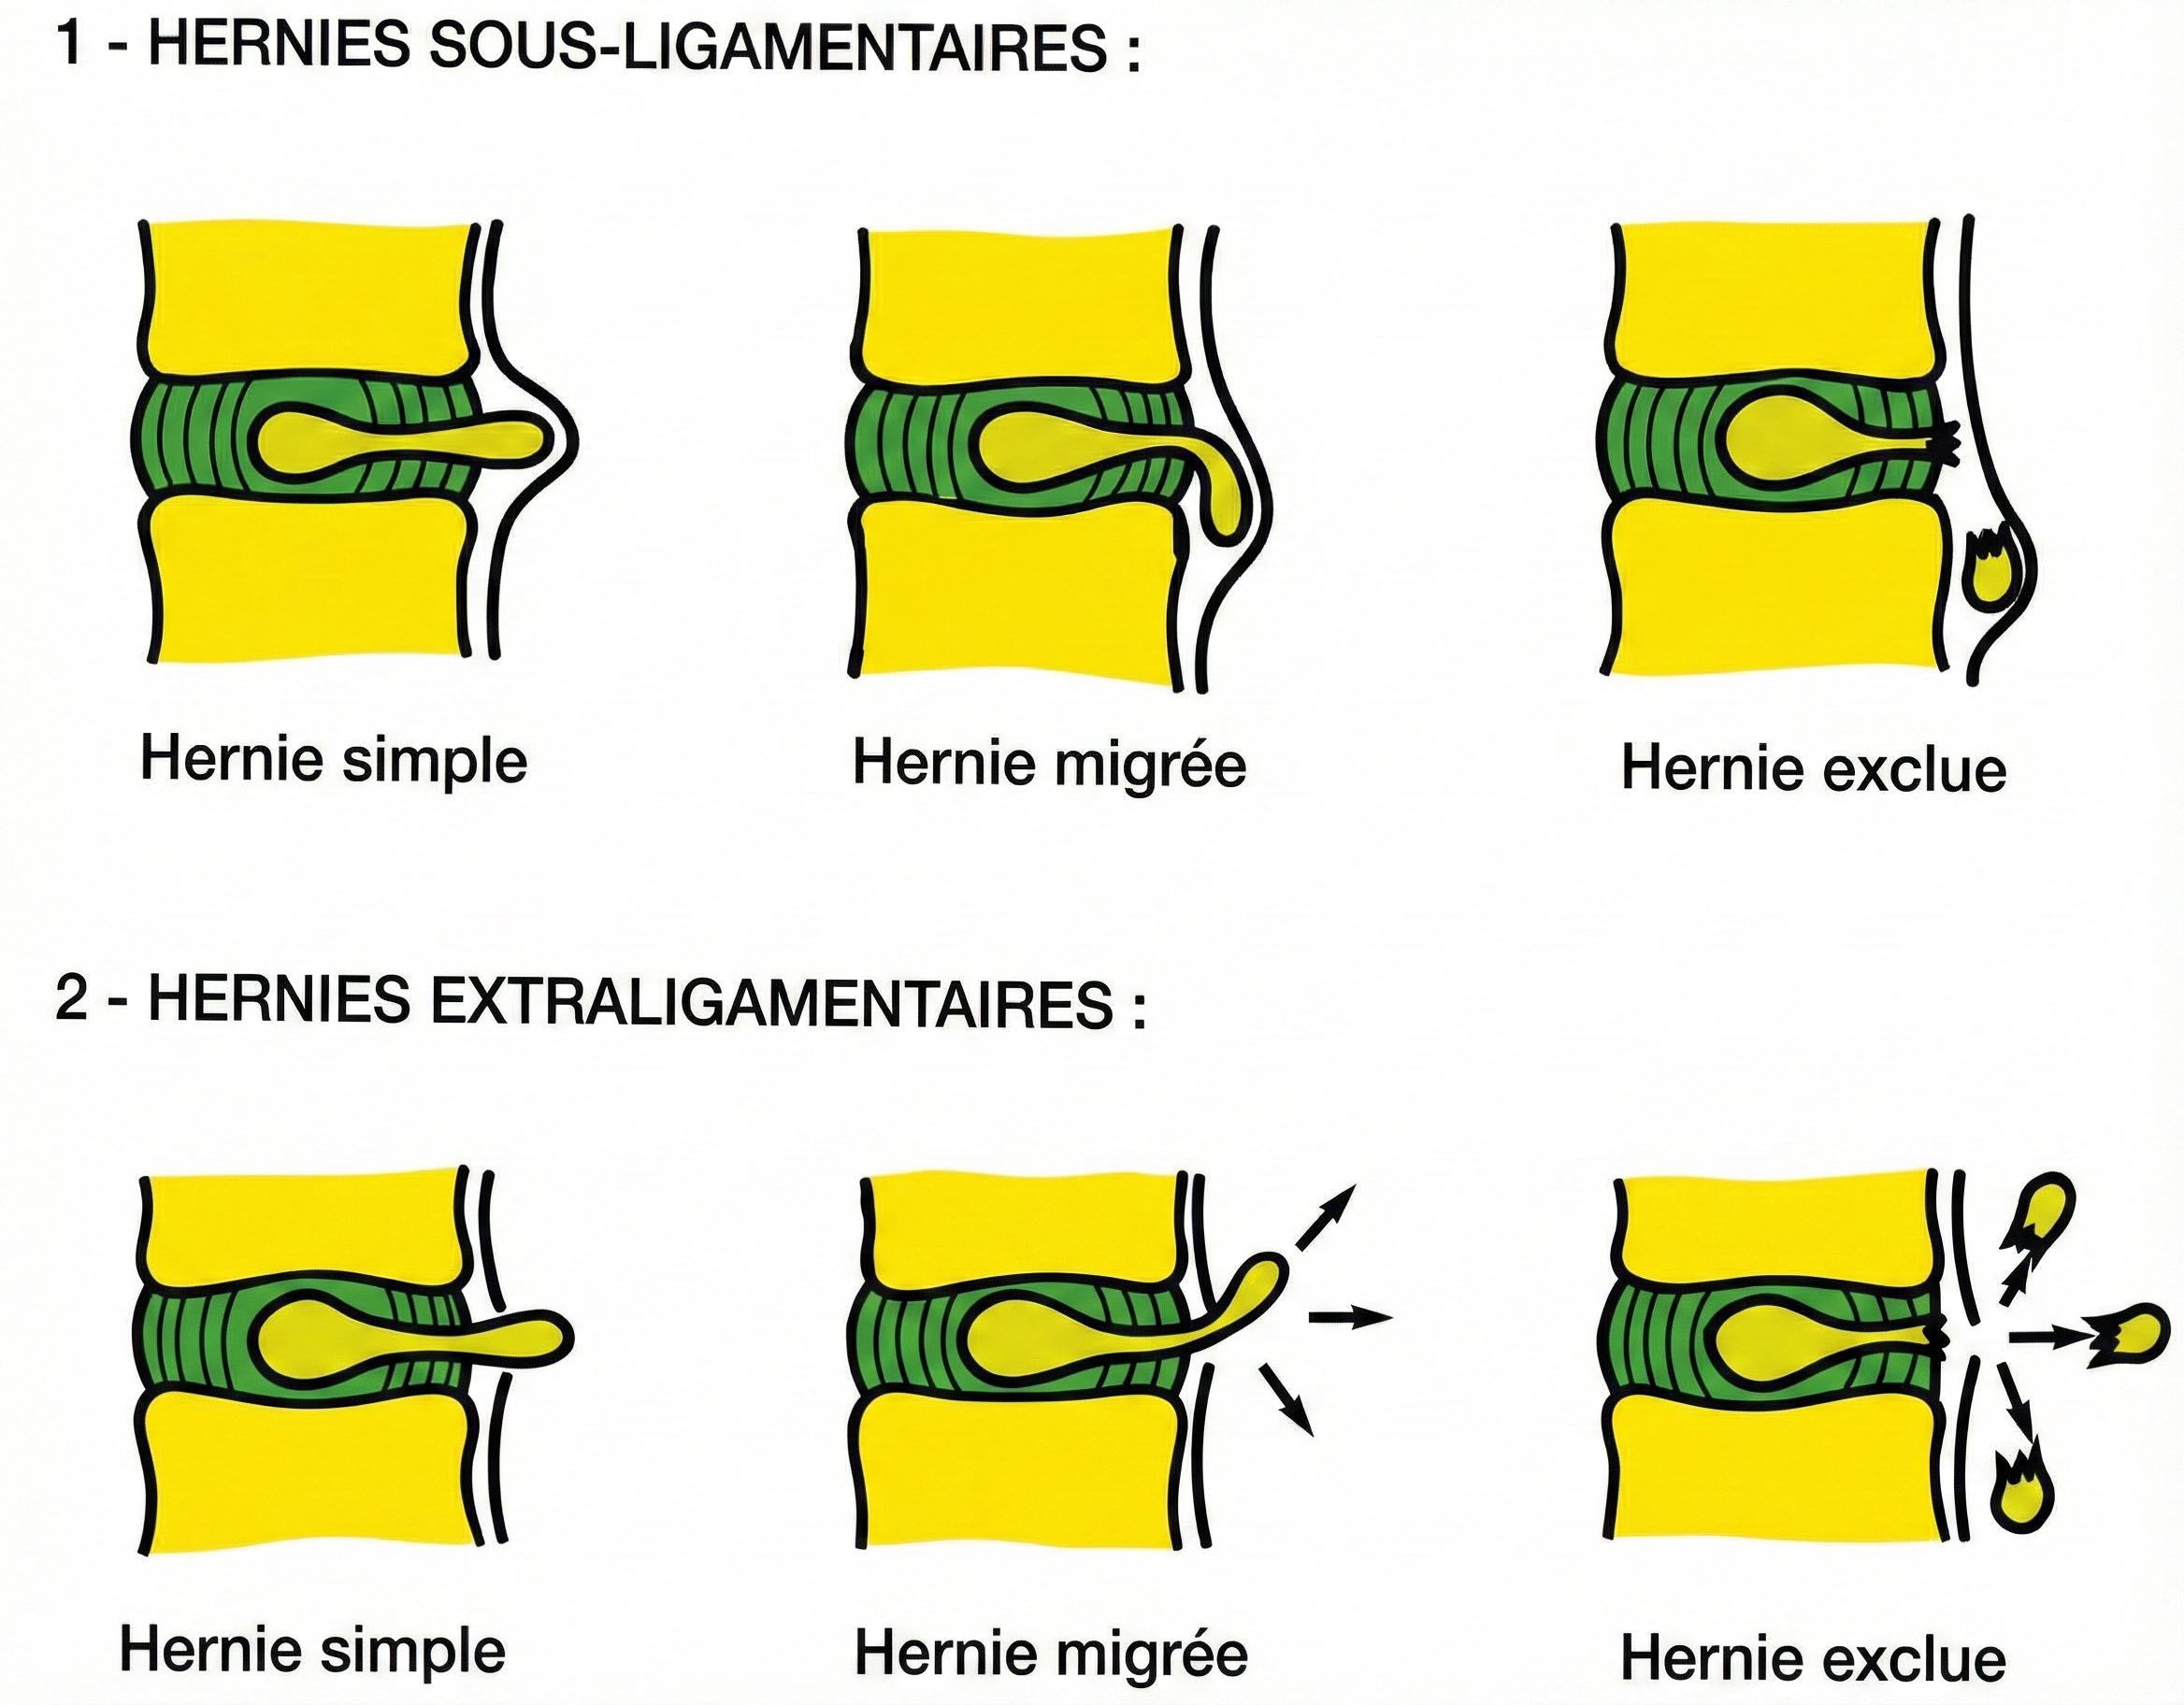

vocabulaire = migration craniale/caudale; fragment exclu épidural

vocabulaire = migration craniale/caudale; fragment exclu épidural